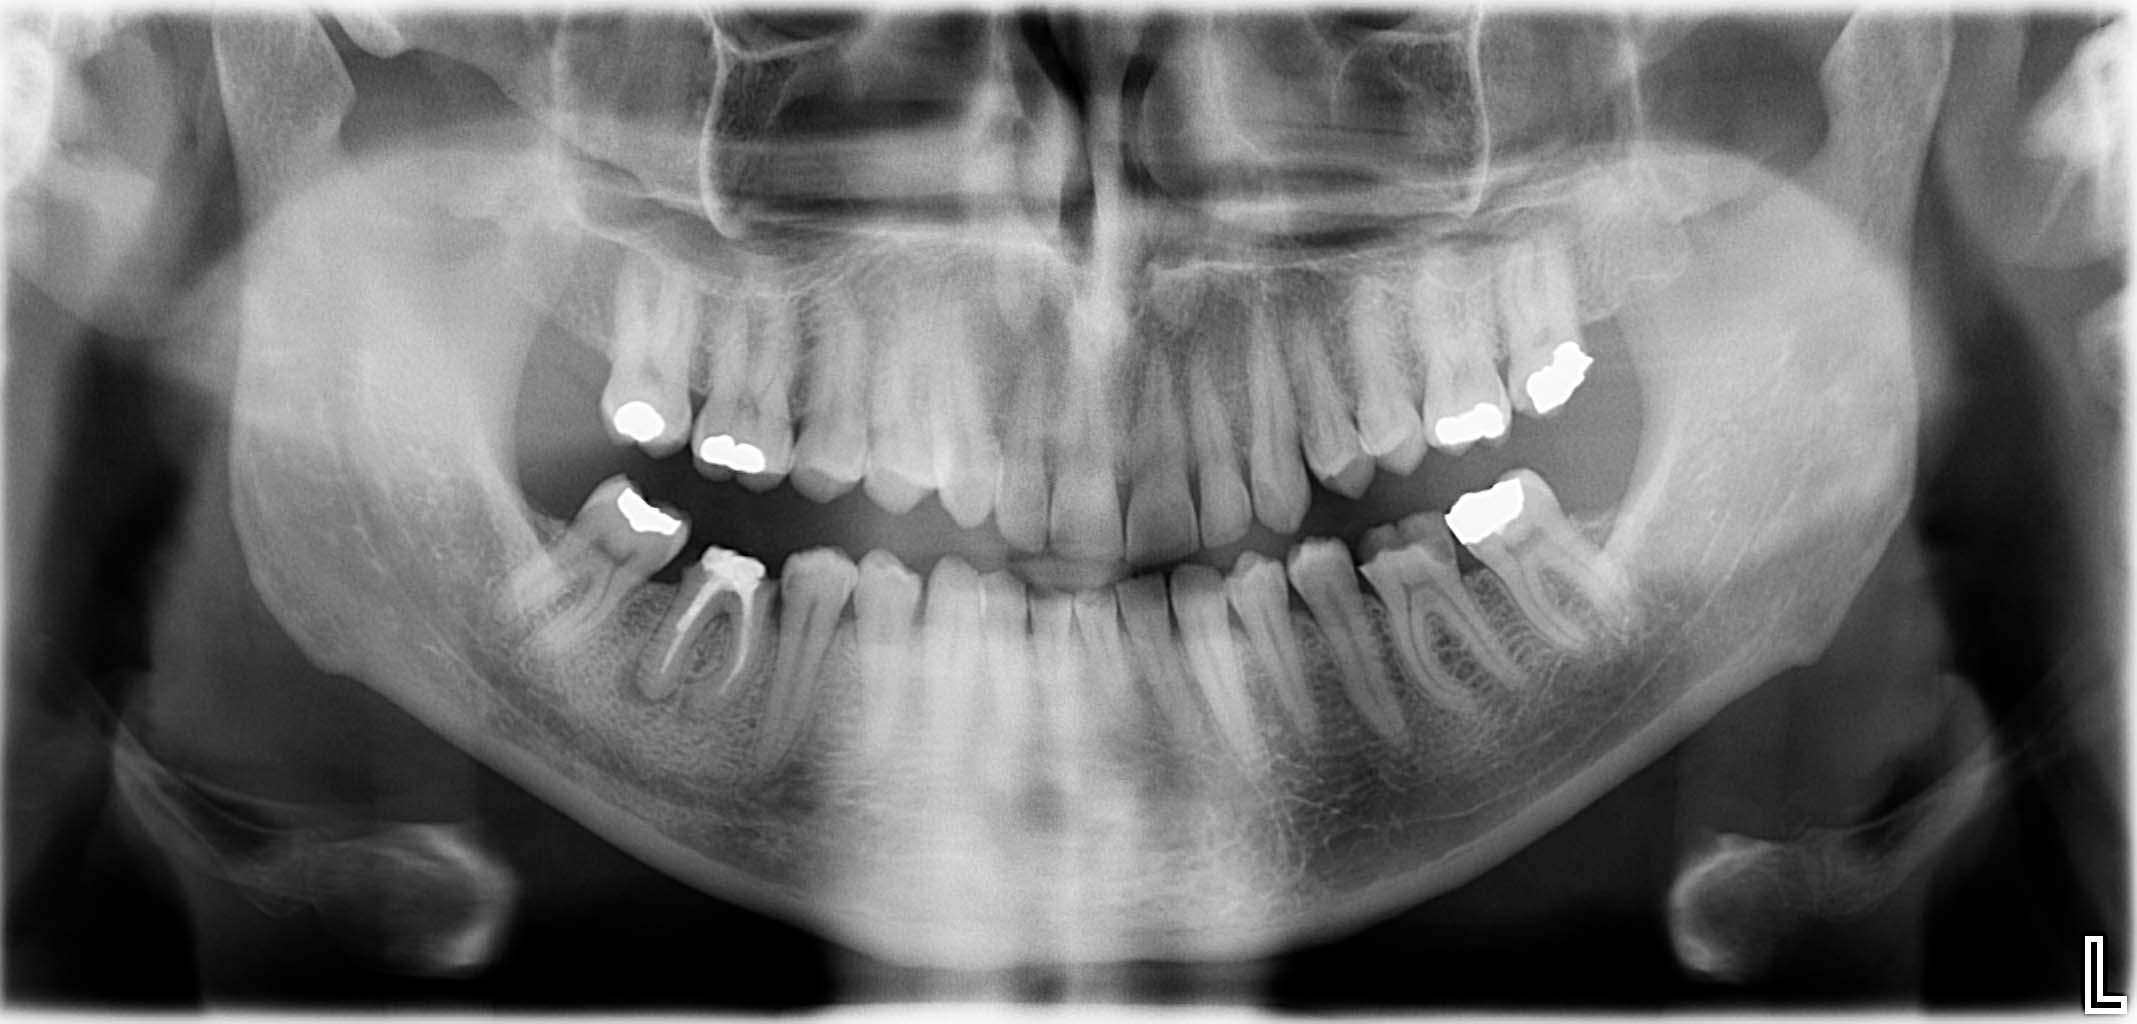

Erfolgreich implantierte Patientenfälle (klinische Fotos)